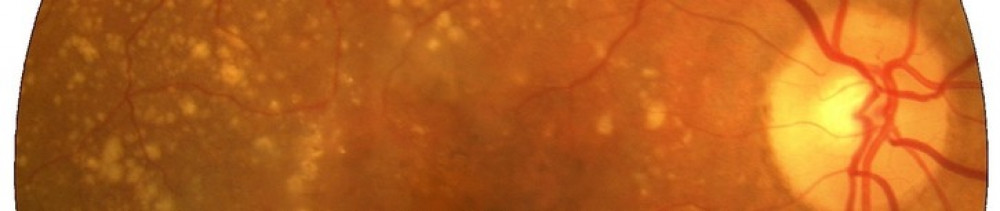

The Medical Retina team diagnoses, monitors and treats conditions that affect the lining of the back of the eye, called the retina. Common conditions include age related macular degeneration, diabetic retinopathy, retinal vein occlusion and inherited retinal diseases.

I was watching TV one day and noticed that straight lines on the screen had gone wavy. I also noticed a dark spot in my vision. I was worried, so I made an appointment with my opticians. The person at my opticians did all the usual tests, like checking my vision and looking into my eyes, but they told me I needed further tests in the hospital as they found signs of possible wet age-related macula degeneration. They explained this can develop when blood vessels grow into the macula at the back of the eye and then leak fluid, which can cause damage.